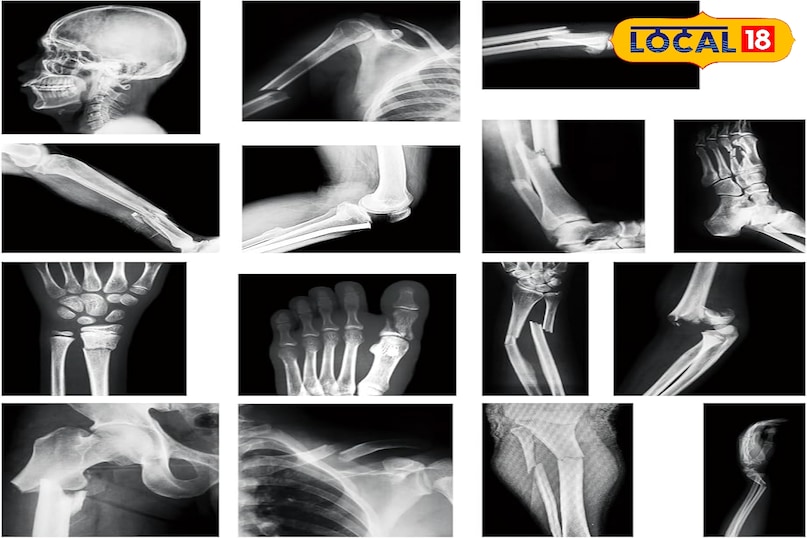

भीलवाड़ा तेजी से राजस्थान का मेडिकल हब बनता जा रहा है और ऑर्थोपेडिक उपचार के मामले में आसपास के जिलों के मरीजों की पहली पसंद बन चुका है. शहर के बड़े अस्पताल टूटी हड्डियों, फ्रैक्चर, जोड़ संबंधी समस्याओं और जोड़ों के प्रत्यारोपण जैसी सेवाओं में आधुनिक तकनीक और अनुभवी डॉक्टरों के साथ प्रभावी इलाज प्रदान करते हैं.

राजस्थान के मेडिकल हब के रूप में तेजी से पहचान बना रहा भीलवाड़ा, ऑर्थो उपचार के मामले में आसपास के जिलों के मरीजों की पहली पसंद बन चुका है. टूटी हड्डियों, जोड़ संबंधी समस्याओं, फ्रैक्चर, दुर्घटना में आई गंभीर चोटों और जोड़ों के प्रत्यारोपण तक, यहां के बड़े अस्पताल आधुनिक तकनीक और अनुभवी डॉक्टरों के साथ प्रभावी उपचार उपलब्ध कराते हैं. खास बात यह है कि कई सरकारी और निजी संस्थान मरीजों को बेहतर चिकित्सा सुविधाएं सस्ती दरों पर उपलब्ध कराते हैं. इसी कारण, चित्तौड़गढ़, राजसमंद, अजमेर और मध्यप्रदेश के क्षेत्रों से भी बड़ी संख्या में लोग इलाज करवाने के लिए भीलवाड़ा पहुंचते हैं.

भीलवाड़ा में ऑर्थो से जुड़े कई प्राइवेट अस्पताल कम बजट में भी अच्छे परिणाम दे रहे हैं. उन्नत मशीनें, CT और MRI सुविधाएं, बोन डेंसिटी टेस्ट, फिजियोथेरेपी सेशन और पोस्ट-सर्जरी रिकवरी के लिए अलग यूनिट्स मरीजों के लिए बेहद मददगार साबित होती हैं. हड्डियों और जोड़ों की बीमारी केवल इलाज तक सीमित नहीं होती; सही रिहैब और थेरपी भी उतनी ही जरूरी होती हैं.